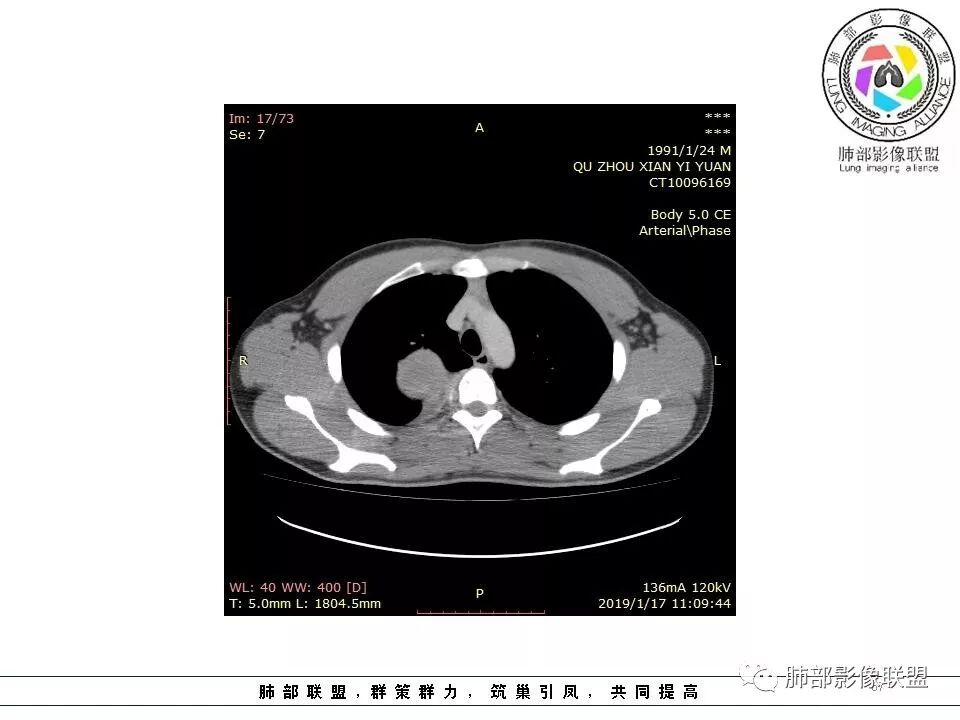

右后纵膈脊柱旁软组织占位,形态规则类圆,边缘光整,肺组织受压,胸膜尾,肋间动脉供血。中度不均匀延迟强化。

后纵隔脊柱旁占位性病变,疾病谱有神经鞘瘤,sft,节细胞瘤,髓外造血。此例有胸膜尾征,蛇纹征 ,延迟强化。考虑胸膜孤立性纤维瘤。看到有供血动脉,但不知道是哪里的血管。

右后纵膈脊柱旁软组织影,与纵隔结构分界不清,形态规则类圆,边缘光整,肺组织受压,胸膜尾,肋间动脉供血。肺动脉推移,中度不均匀延迟强化。考虑神经来源,神经鞘瘤,神经纤维瘤二者不易鉴别。

青年男性,间断胸痛;右侧脊柱旁可见一类圆形软组织密度影,密度欠均匀,增强扫描呈轻中度持续强化,邻近肺组织及肺动脉推移,可见肋间动脉供血,部分胸膜下脂肪可见,部分层面似见与右侧椎间孔相连。考虑后纵隔神经源性肿瘤。

病灶定位脏层胸膜,肺组织受挤压,有胸膜尾征,动脉期可见血管支配,考虑肺动脉供血,静脉期,强化增强明显,符合快进慢出特点,病灶内可见低密度区,考虑胸膜孤立纤维瘤。

青年男性,间断胸痛。右后纵膈脊柱旁软组织占位,形态规则类圆,边缘光整,肺组织受压,D字征,胸膜尾,肋间动脉供血。中度不均匀延迟强化。无支气管进入考虑来源于肺外、肿块与脊柱间未见明显脂肪间隙,考虑来源于胸膜外,考虑神经源性肿瘤,建议穿刺活检。

右肺占位,跨越上叶后段、下叶背,边缘光滑,瘤肺界面清,见肺压缩缘(线样不张`强化),见胸膜尾征,胸膜下脂肪未见明显增厚,肋骨丶脊柱未见侵袭及受压,渐进性丶地图样强化,冠状位似见体循环供血

诊断:SFT(来源壁层胸膜?一般小于20%)

脏层胸膜主要由支气管动脉和肺动脉供血,壁层胸膜主要由支气管动脉,胸廓内动脉、肋间动脉供血

如果是肋间动脉,就不可能是脏层胸膜,可以是壁层或者纵膈

但是这个病人,肋间动脉供血吧,我倾向胸膜

边缘光滑,宽基底与胸壁相连,跨叶裂,叶裂稍前推,血管、支气管前移。

肋间动脉供血,强化尚均匀,逐步强化

供血,体外供血,体循环,要么是壁层胸膜,要么胸膜外的,脏层胸膜应该是对内供血。病变里面的血管,除非是非常粗大迂曲的血管,不然,我不认为是其特点。

脏层胸膜肺内供血,壁层胸膜体外供血

这个病人不是肺动脉与支气管动脉供血,是肋间动脉供血

2.肋间动脉病供血也提示肿块来自后纵隔?